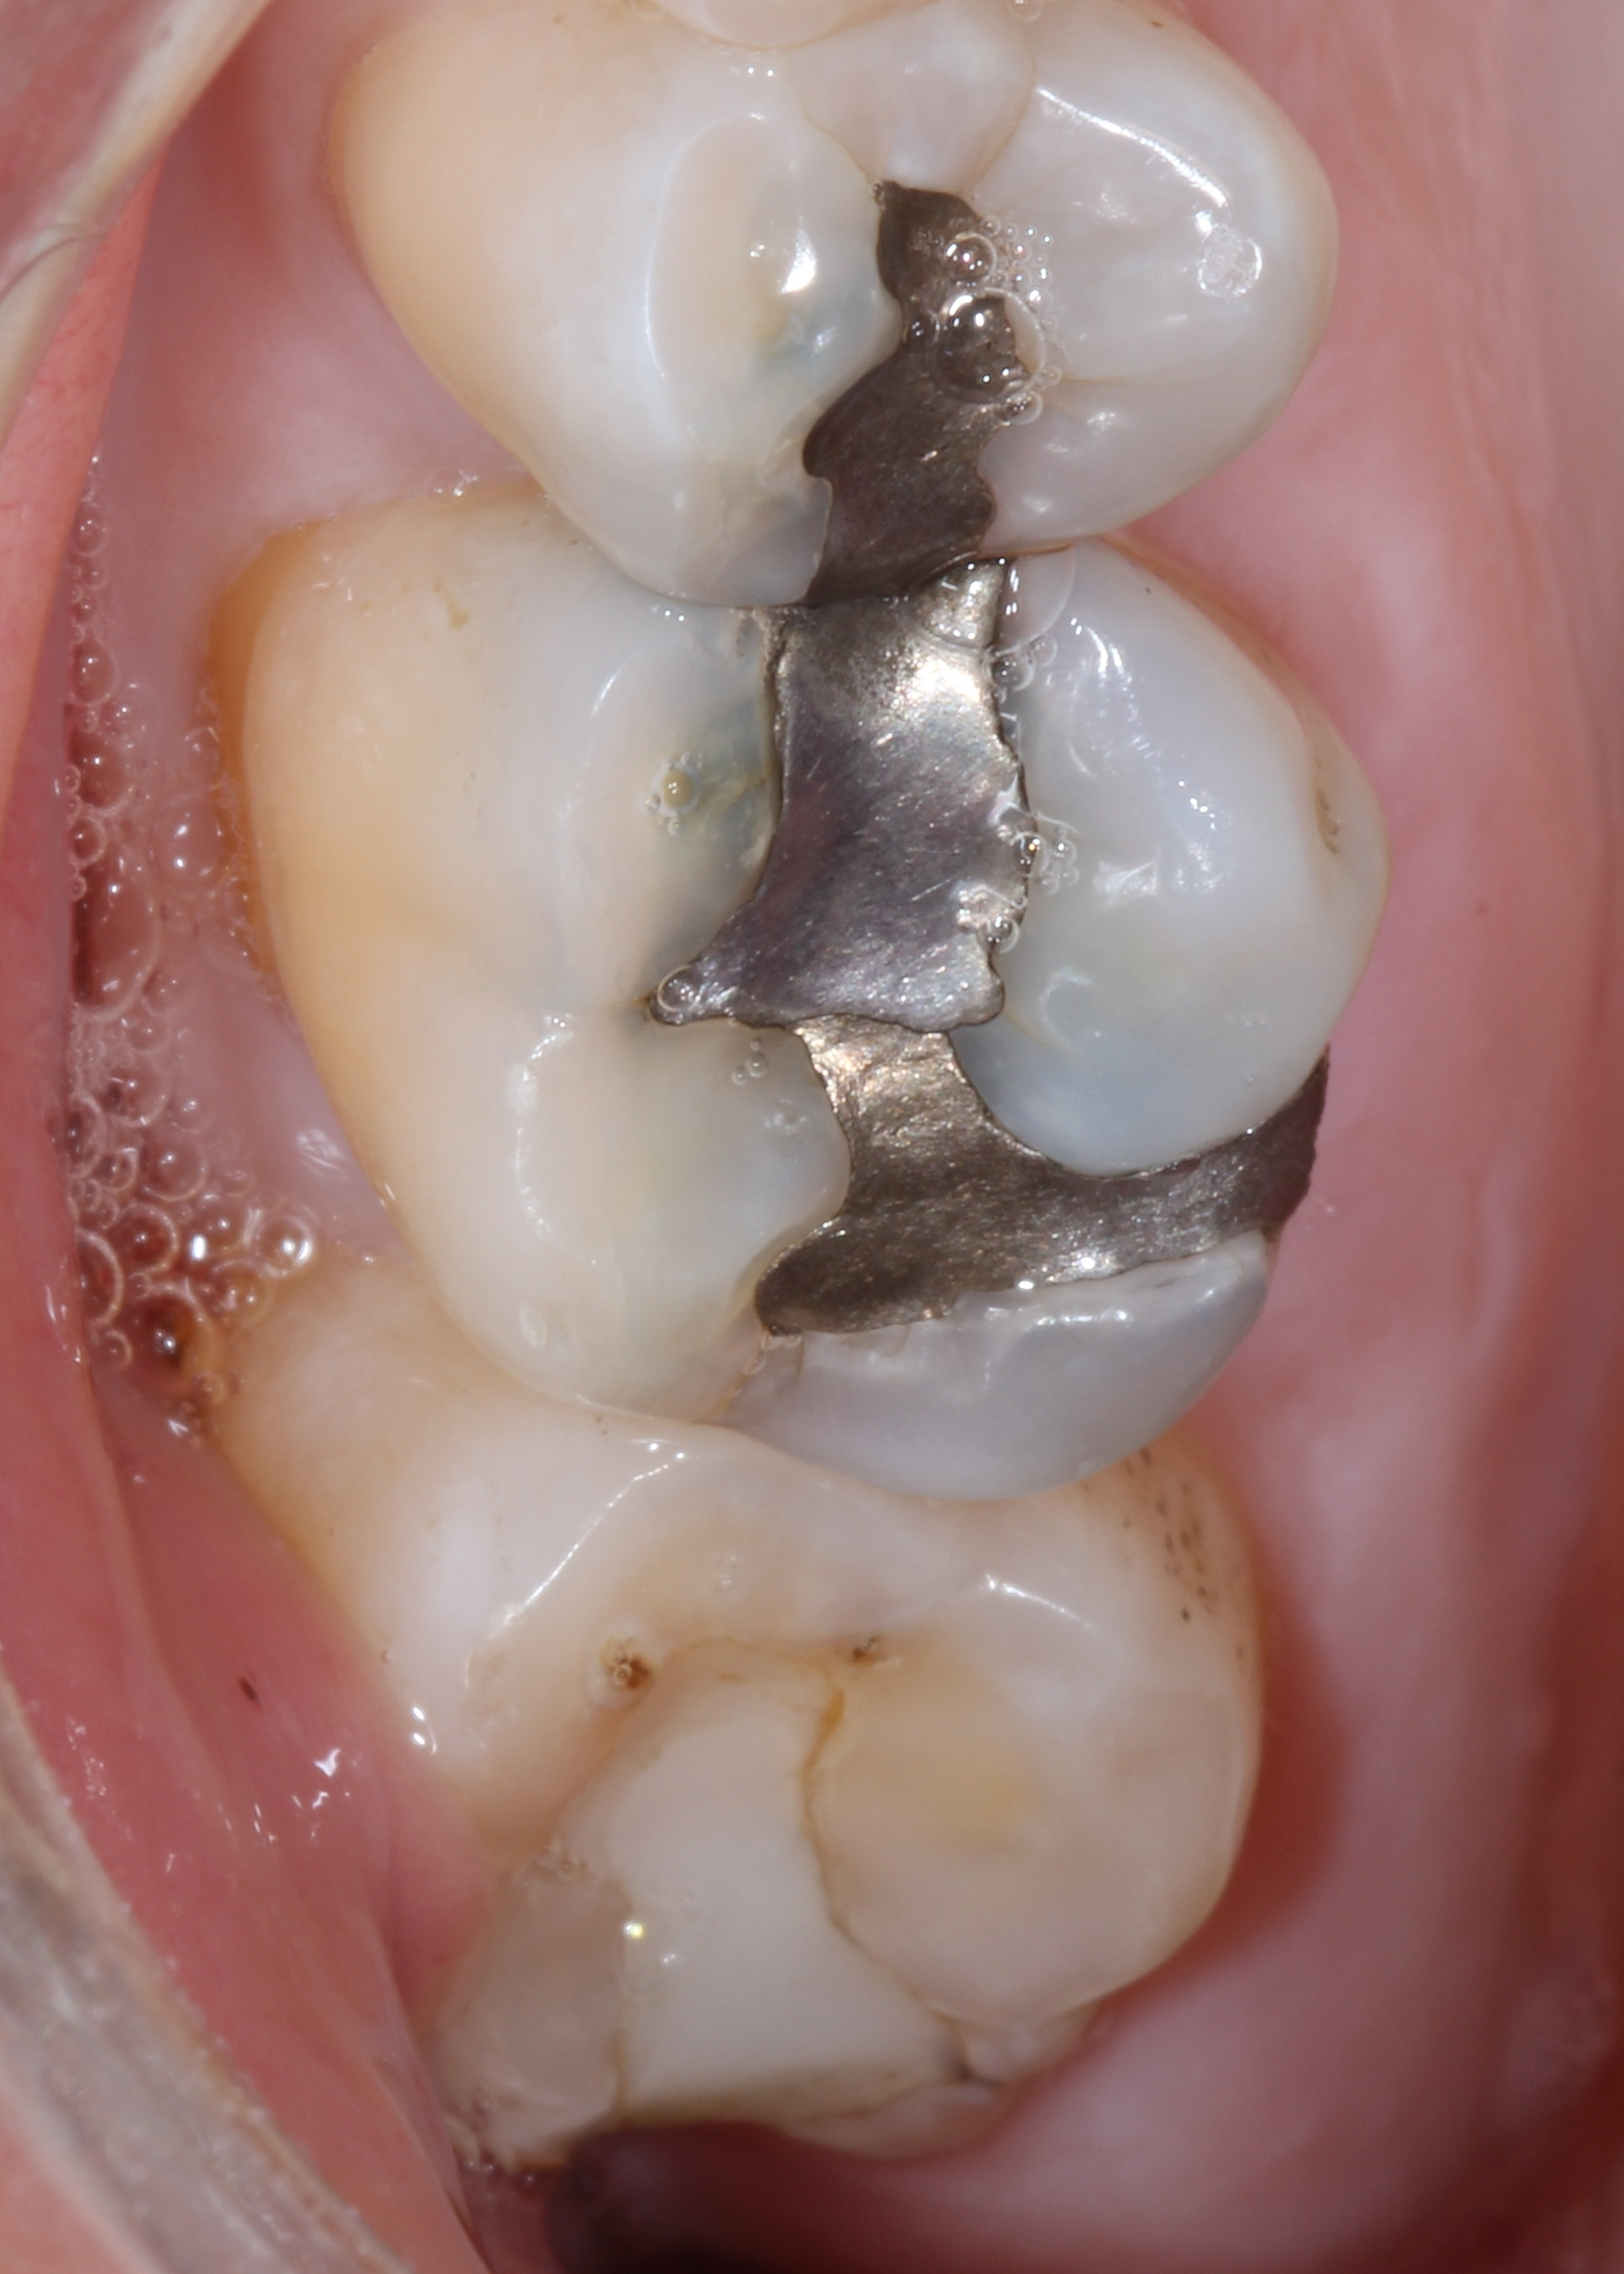

Fig. 2

In this clinical situation, the patient had been complaining of pain on the maxillary left side. Visually, the restorations appeared worn but the margins were intact (Fig. 1). A bitewing radiography did not reveal any radiolucency around the restorations on the teeth (Fig. 2).

Bitewing radiographs may not be the ideal for detecting enamel secondary caries,3, 4, 5 particularly if they are located on the occlusal or smooth surfaces. The restoration also masks the ability of radiographs to detect caries along the preparation walls.6 All of these factors create difficulties in determining the source of pain.